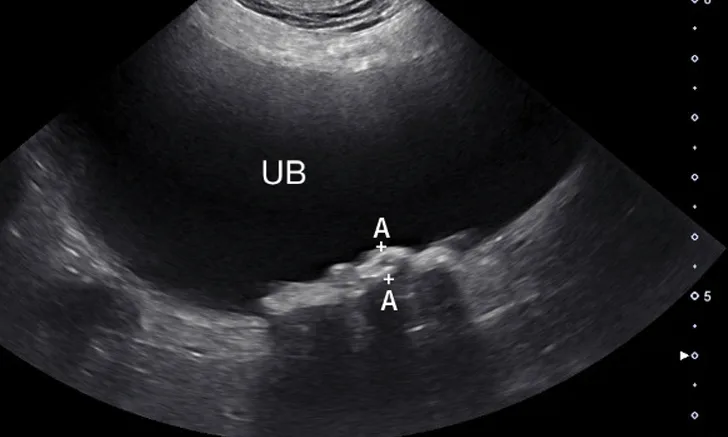

FIGURE 1

Sagittal image of the urinary bladder (UB; cranial aspect toward the left side of the image). Numerous calculi (between calipers) are present along the dependent aspect of the urinary bladder (away from the probe with the patient in dorsal recumbency) and, unlike in cases of neoplasia, are hyperechoic and cast a clean acoustic shadow.